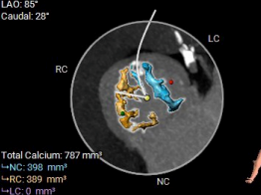

主动脉瓣钙化积分:787mm2

• 瓣叶重度钙化